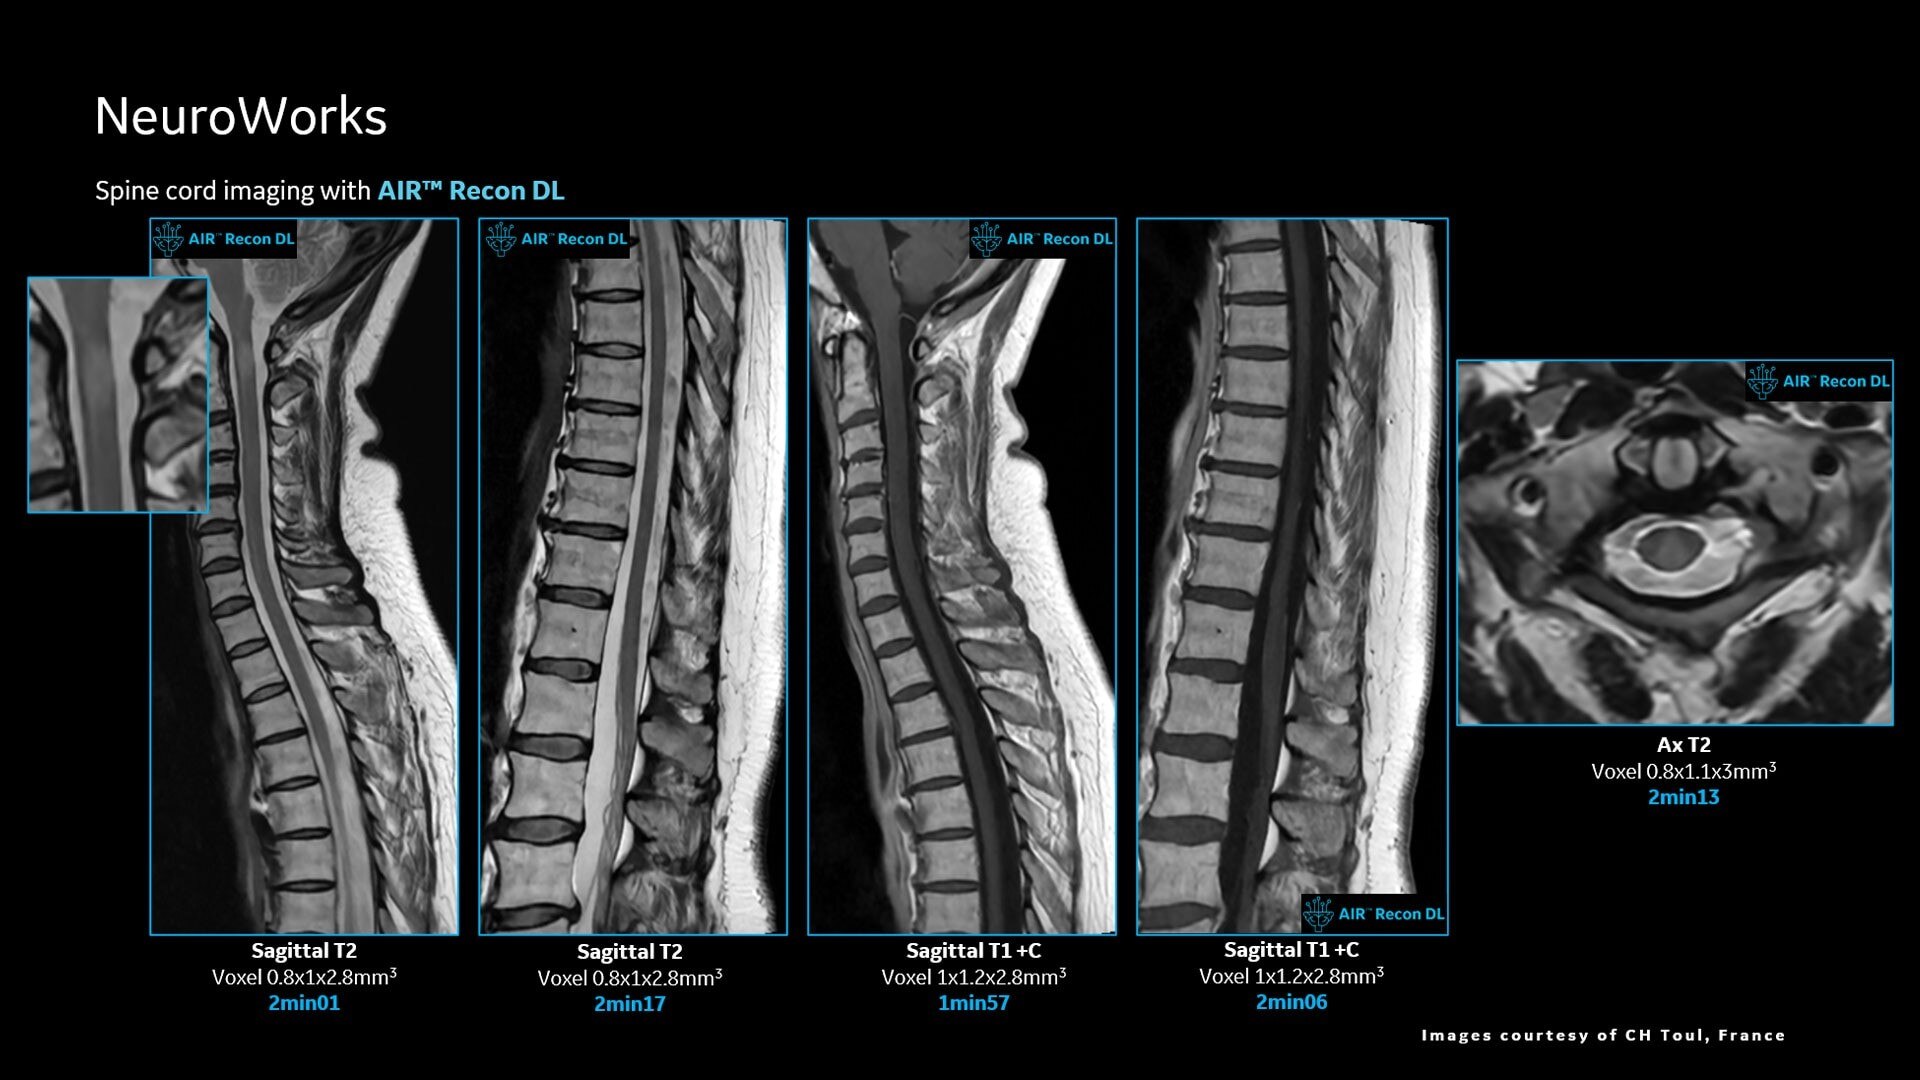

AIR™ Recon DL improves SNR and image sharpness, enabling shorter scan times

Up to 50% faster acquisition time with AIR™ Recon DL